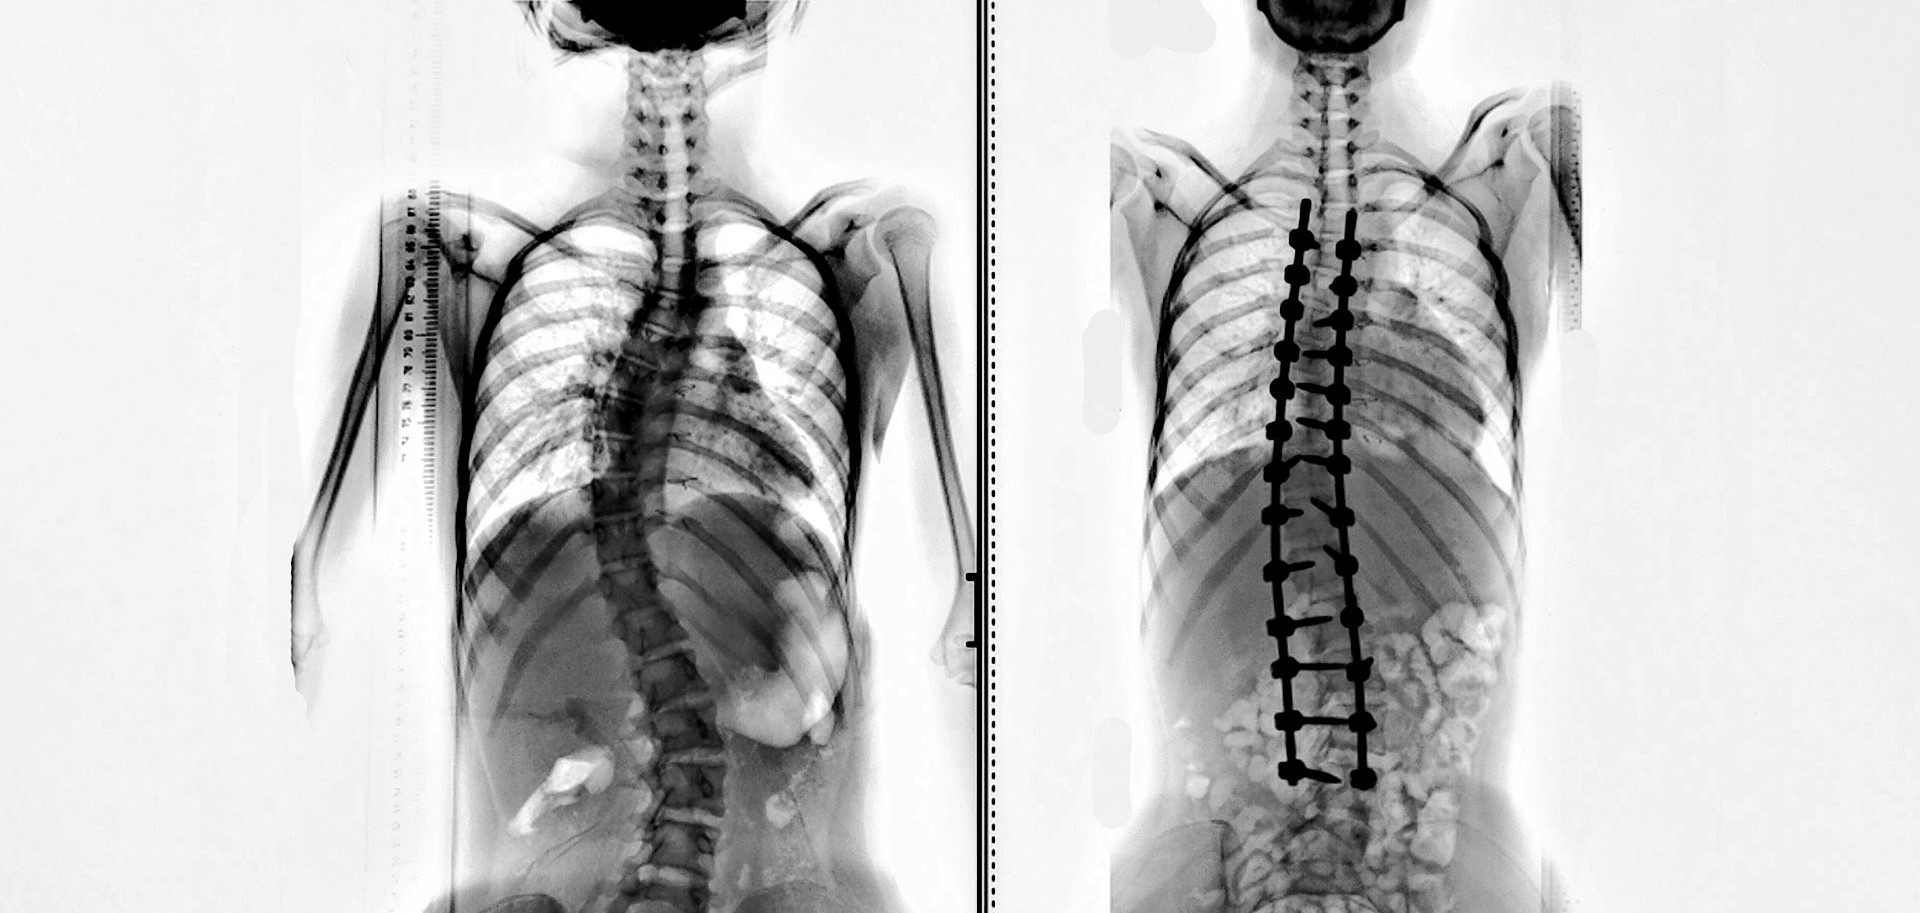

If scoliosis is severe, your doctor may recommend surgery to deal w ith the curve. This could be through spinal fusion, where your doctor w ill fuse together vertebrae in the spine to help hold the spine straight.

Another form of surgery is with an expanding rod. This is usually suggested for children who have rapidly developing scoliosis and the rod can be lengthened every 3 to 6 months.